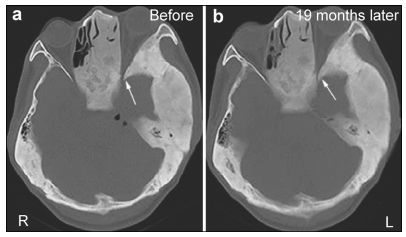

2 Case study 2.1 History and examinationA 30-year-old man presented with a 20-day history of clear discharge from his right nostril. He suffered from a mild head trauma 40 days before counseling at our institution. Laboratory tests of the discharge showed a glucose level of 3.73 mmol/L. This high glucose level suggested that the discharge was CSF. Physical examination showed that the patient’s left eye and left frontal part were more prominent than the equivalent right side. According to the patient’s recall, these symptoms first appeared at the age of twenty and had changed slowly since then. Computed tomography (CT) cisternogram located the site of the defect in the posterior wall of the right frontal sinus and demonstrated the evident expansion of multiple skull bones (Figure 1). Lumbar puncture was done and intracranial pressure was 150 mm H2O.

| Figure 1 (a, b) A computed tomography (CT) scan demonstrating the expansion of multiple skull bones. The involved bones present with various appearances of mixed radio-dense/radio-lucent lesions, which can be described as “ground-glass”, “lytic”, and “cystic”. Left: Axial CT cisternography demonstrates a fistula at the posterior wall of the right frontal sinus (white arrow). The density of both frontal involved bones is slightly lower than for other skull bones. Right: A coronal CT scan demonstrates pneumocephalus in the right frontal lobe (black arrow). |

The first was pathological changes in the skull bone. FD is characterized by the excessive formation of fibrous tissue in the bone marrow and the destruction of normal bone in conjunction with abnormal bone formation and increased osteoclast activity[11]. Normal bone tissue is replaced by the gradual abnormal pro-liferation of fibrous tissue[9]. These pathological changes weaken the structural integrity of the involved bones[12]. Under slight stress, these bones tend to deform and might even fracture[13]. As the limbs, especially both lower limbs, usually bear most of the mechanical stress during daily life, pathologic fractures often occur in these bones with FD. Without significant stress, skull bones with FD rarely fracture. However, when a CFD patient suffers from head trauma, these skull bones might fracture more easily than normal bones. In our patient, CFD was involved in multiple skull bones, including the right frontal bone. A CT scan indicated a low density of the involved right frontal bone (Figure 1), and enhanced MRI showed evident enhan-cement of the right frontal sinus wall (Figure 4). This suggested that the bone in right frontal sinus wall contained numerous small vessels and fibrous elements[3], which would decrease the strength of the bone. These pathological changes increased the risk of fractures after head trauma. As the enhanced MRI was performed after surgery, the enhancement of right frontal sinus posterior wall might also be caused by a healing reaction. However, because the anterior wall of right frontal sinus and surrounding involved bones were also enhanced, it was reasonable to presume that the enhanced effect was mainly caused by pathological changes due to FD.

The second factor was increased intracranial pressure associated with CFD that might contribute to CSF rhinorrhea. In this case, a CT scan demonstrated significant thickening and expansion of multiple skull bones, decreasing the cranial cavity (Figure 1). However, before the head trauma, this patient did not have symptoms associated with increased intracranial pressure, including headache, nausea and vomiting. This suggested that before the trauma, the patient’s intracranial pressure was well compensated. However, as the cranial cavity was decreased after trauma, this compensation for a higher intracranial pressure was constrained. During the period of trauma, both the swelling of the brain and pneumocephalus might have contributed to the increased intracranial pressure. Without good compensation ability, the patient’s intracranial pressure increased. Although the intrac-ranial pressure measured by lumber puncture before the fistula repair surgery was normal, this might have been associated with an alleviation of the swelling brain after a forty-day recovery and the discharge of CSF through the fistula. To increase the cranial cavity, we contoured the excised bone to be thinner before it was placed back during the fistula repair surgery. This treatment effect was satisfactory (Figure 3).

In this case, CSF rhinorrhea began about twenty days after the head trauma. Initially, the fistula might be temporarily blocked by tissues such as the brain, granulation tissue, and sinus mucosa[14]. Sometimes, CSF leakage can occur more than 3 months after head trauma, termed delayed onset of CSF rhinorrhea[15]. Spontaneous CSF rhinorrhea has also been reported in various anterior cranial base pathologies, such as osteoma, pituitary adenoma, primary empty sella, and chordoma[16-19]. Spontaneous CSF rhinorrhea may be caused by pathological invasion of the cranial base or intracranial hypertension[20, 21]. Although it was reported that CFD may have a tendency for spontaneous CSF leakage[22], there have been no related case reports published to the best of our knowledge. Our case report may provide support to the idea that CFD may have a tendency for spontaneous CSF leakage. However, in some situations, CFD may decrease the risk of CSF rhinorrhea. For example, if the cavity of the paranasal sinus is filled with expanded bone tissue as in the left frontal sinus of our patient (Figure 1), CSF cannot drain out through the paranasal sinus. Furthermore, if the wall of the paranasal sinus contains more osseous elements, the bone strength is stronger and less likely to fracture. Therefore, whether CFD increases the risk of CSF rhinorrhea in different situations needs to be evaluated.

The surgical treatment of CFD aims to correct the facial deformity in most cases and restore the obliterated foramina, when it the cause of problems. However, this can result in recurrence in 15%-20% of all cases, especially during the growth period[7, 23]. The most devastating consequence of CFD is the loss of vision due to optic nerve compression (ONC). There has been significant controversy regarding the manage-ment of FD of the sphenoid bones that encase the optic nerve, particularly in patients whose vision is normal. A meta-analysis[24] showed that most patients with CFD remain asymptomatic during long-term follow-up, and therefore expectant management is recommended in asymptomatic patients even in the presence of radiological evidence of ONC. Lee et al.[5]recommended that FD in the skull base around vital structures, including the optic nerve, should be managed according to the clinical examination and regular diagnostic imaging and observation is appro-priate in asymptomatic patients. When visual change or vision loss occurs due to ONC, decompression surgery can be performed. In this case, the patient’s age was over 30 years and a CT scan of the involved skull bones showed a mixed appearance (Figure 1). This indicated that the involved bones had entered a stable period. However, nineteen months later, sight in the patient’s left eye had decreased. A CT scan showed that compression of the left optic nerve was more severe than at nineteen months previously (Figure 5). MAS was suspected. Unfortunately, the patient refused to undergo the proposed decompression surgery and laboratory tests of serum hormones.